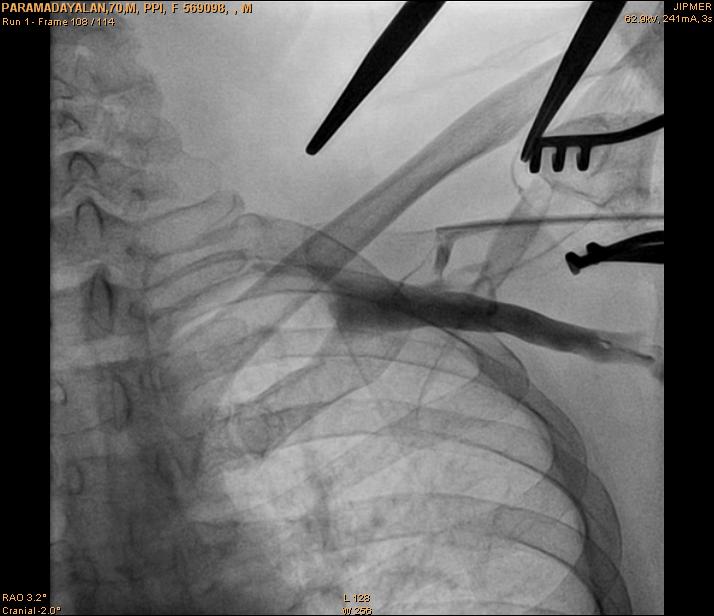

Axillary vein puncture

• Fluoro guided

• Junction of clavicle and first rib

• Walk along first rib